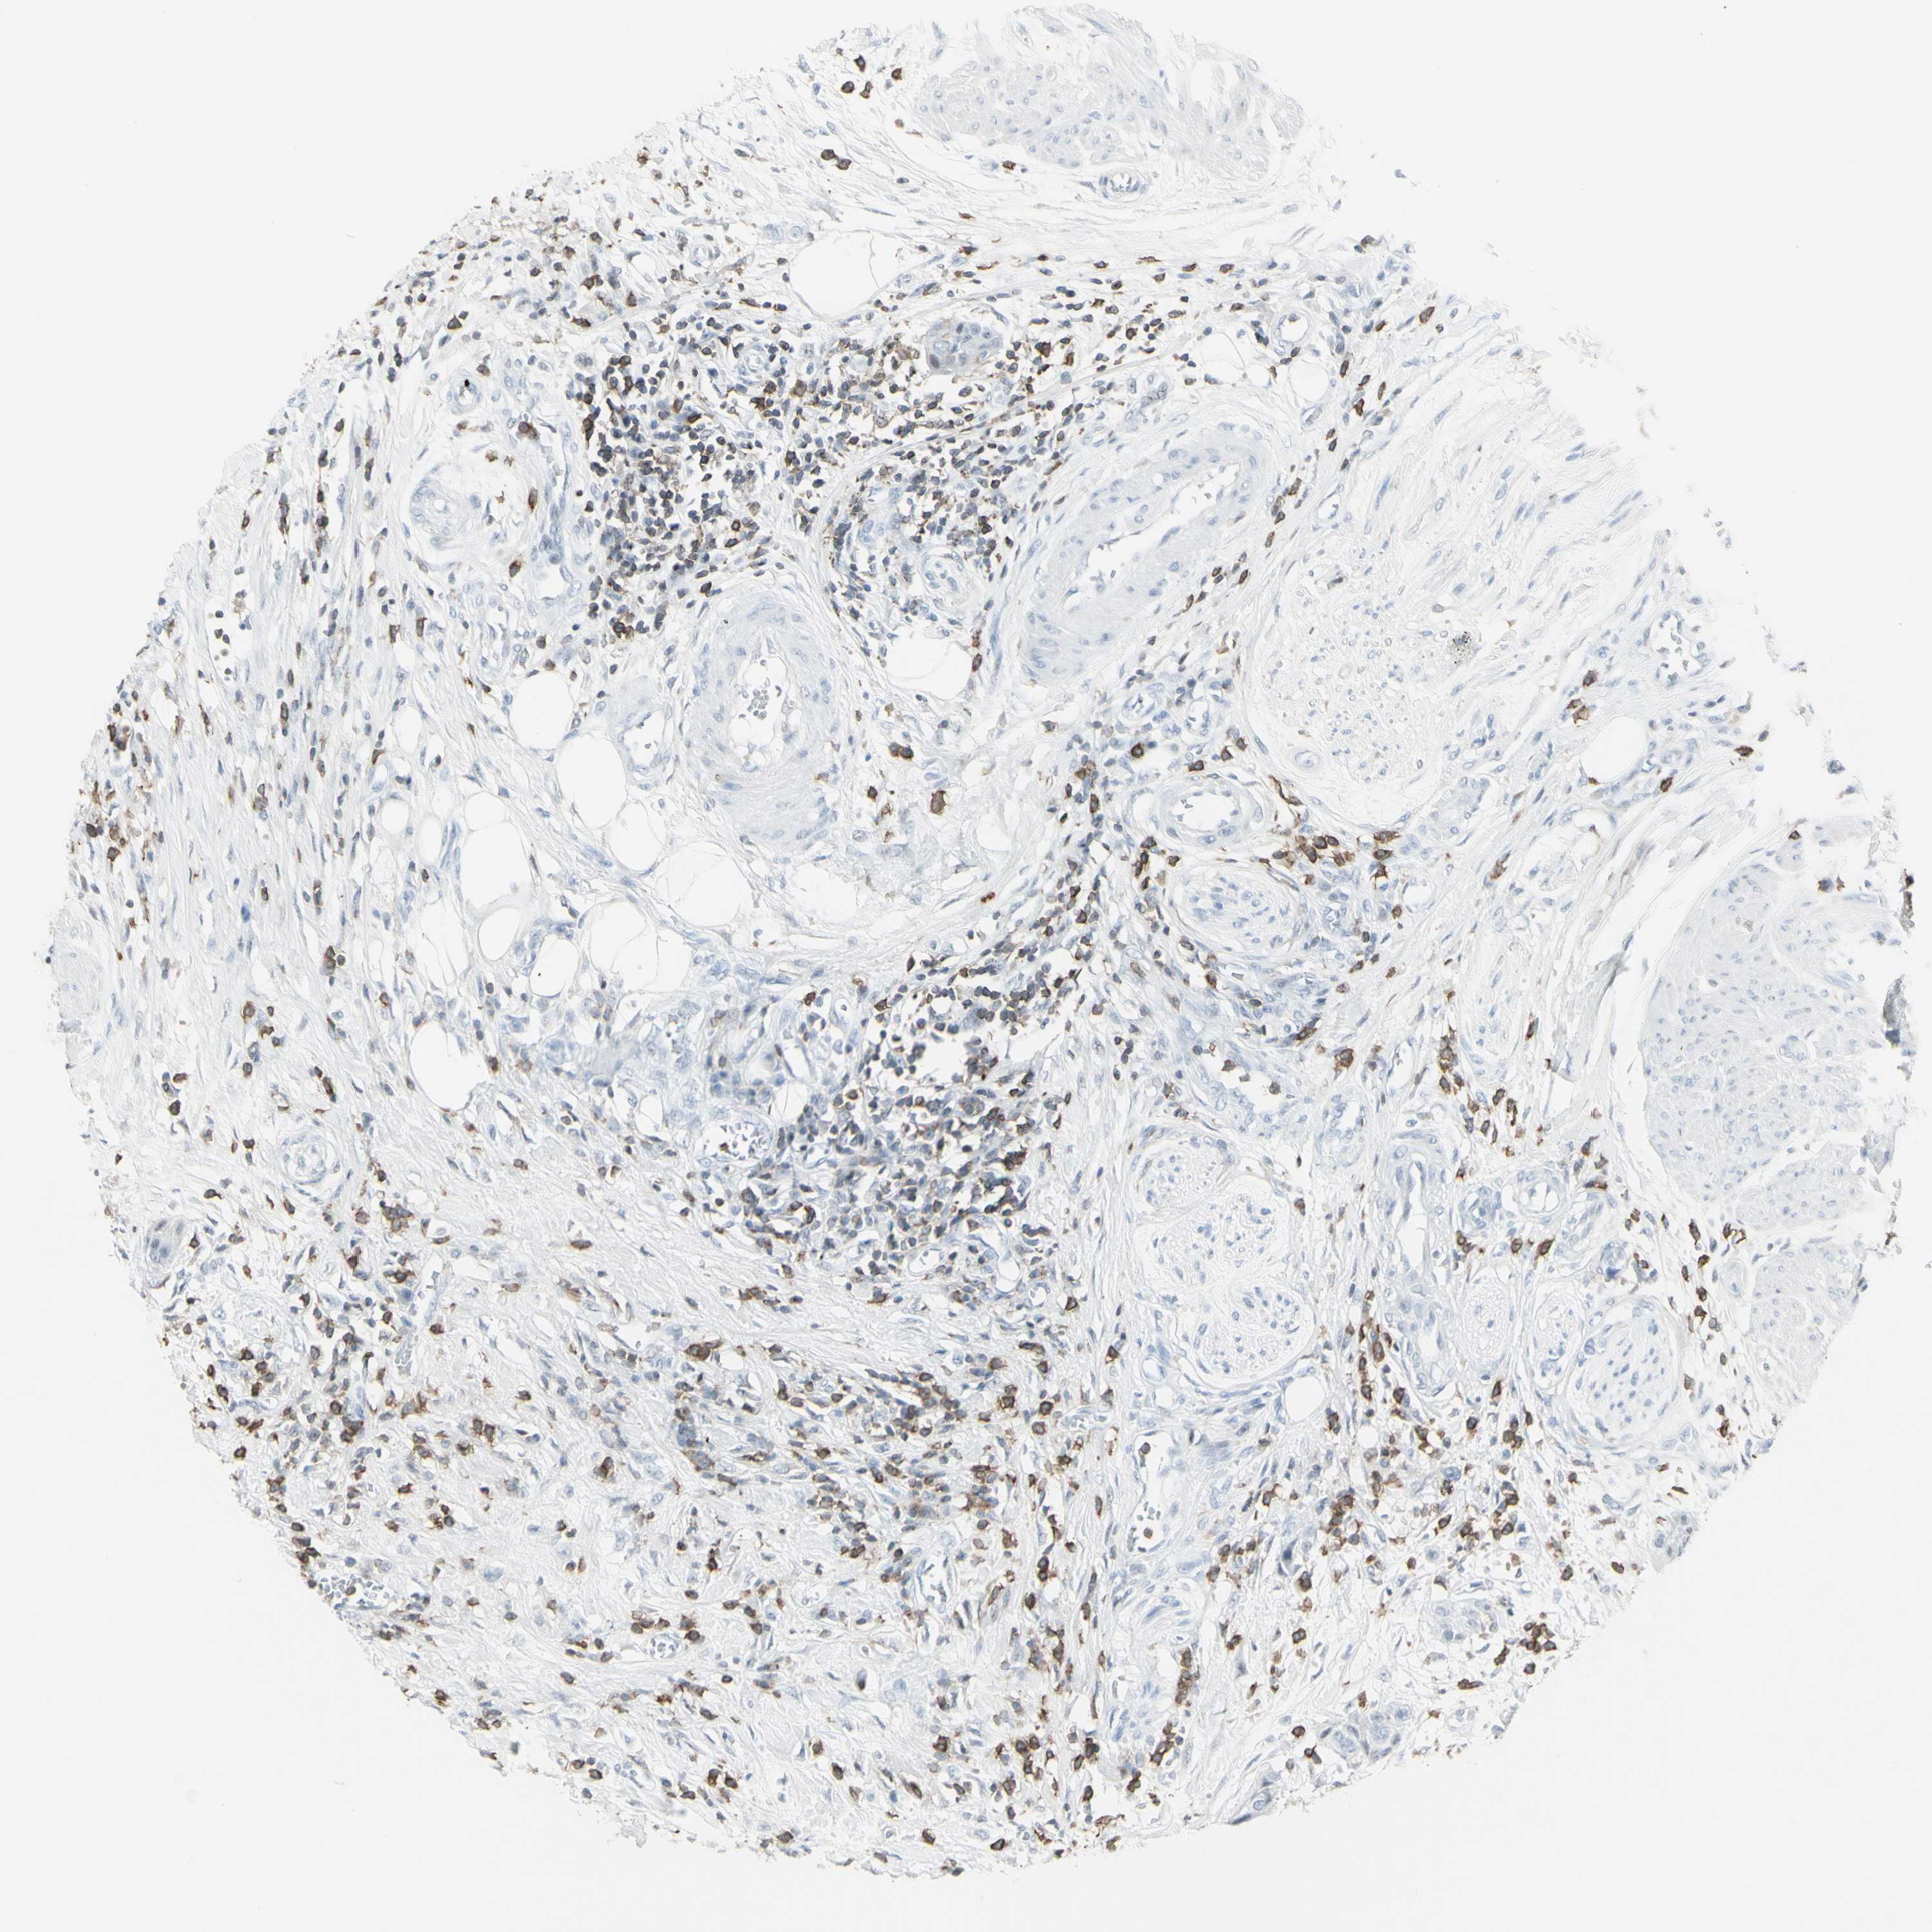

UROTHELIAL CANCER - Protein expressioni

A mouse-over function shows sample information and annotation data. Click on an image to view it in a full screen mode. Samples can be filtered based on level of antibody staining by selecting one or several of the following categories: high, medium, low and not detected. The assay and annotation is described here.

Antibody stainingi

Antibody staining in the annotated cell types in the current human tissue is reported as not detected, low, medium, or high, based on conventional immunohistochemistry profiling in selected tissues. This score is based on the combination of the staining intensity and fraction of stained cells.

Each image is clickable and will lead to virtual microscopy that enables deeper exploration of all samples and also displays staining intensity scores, fraction scores and subcellular localization as well as patient and tissue information for each sample.

Antibody HPA010964

Staining

High

Medium

Low

Not detected

Intensity

Strong

Moderate

Weak

Negative

Quantity

>75%

75%-25%

<25%

None

Location

Nuclear

Cytoplasmic/membranous

Cytoplasmic/membranous,nuclear

Urothelial carcinoma, Low grade

Urothelial carcinoma, High grade